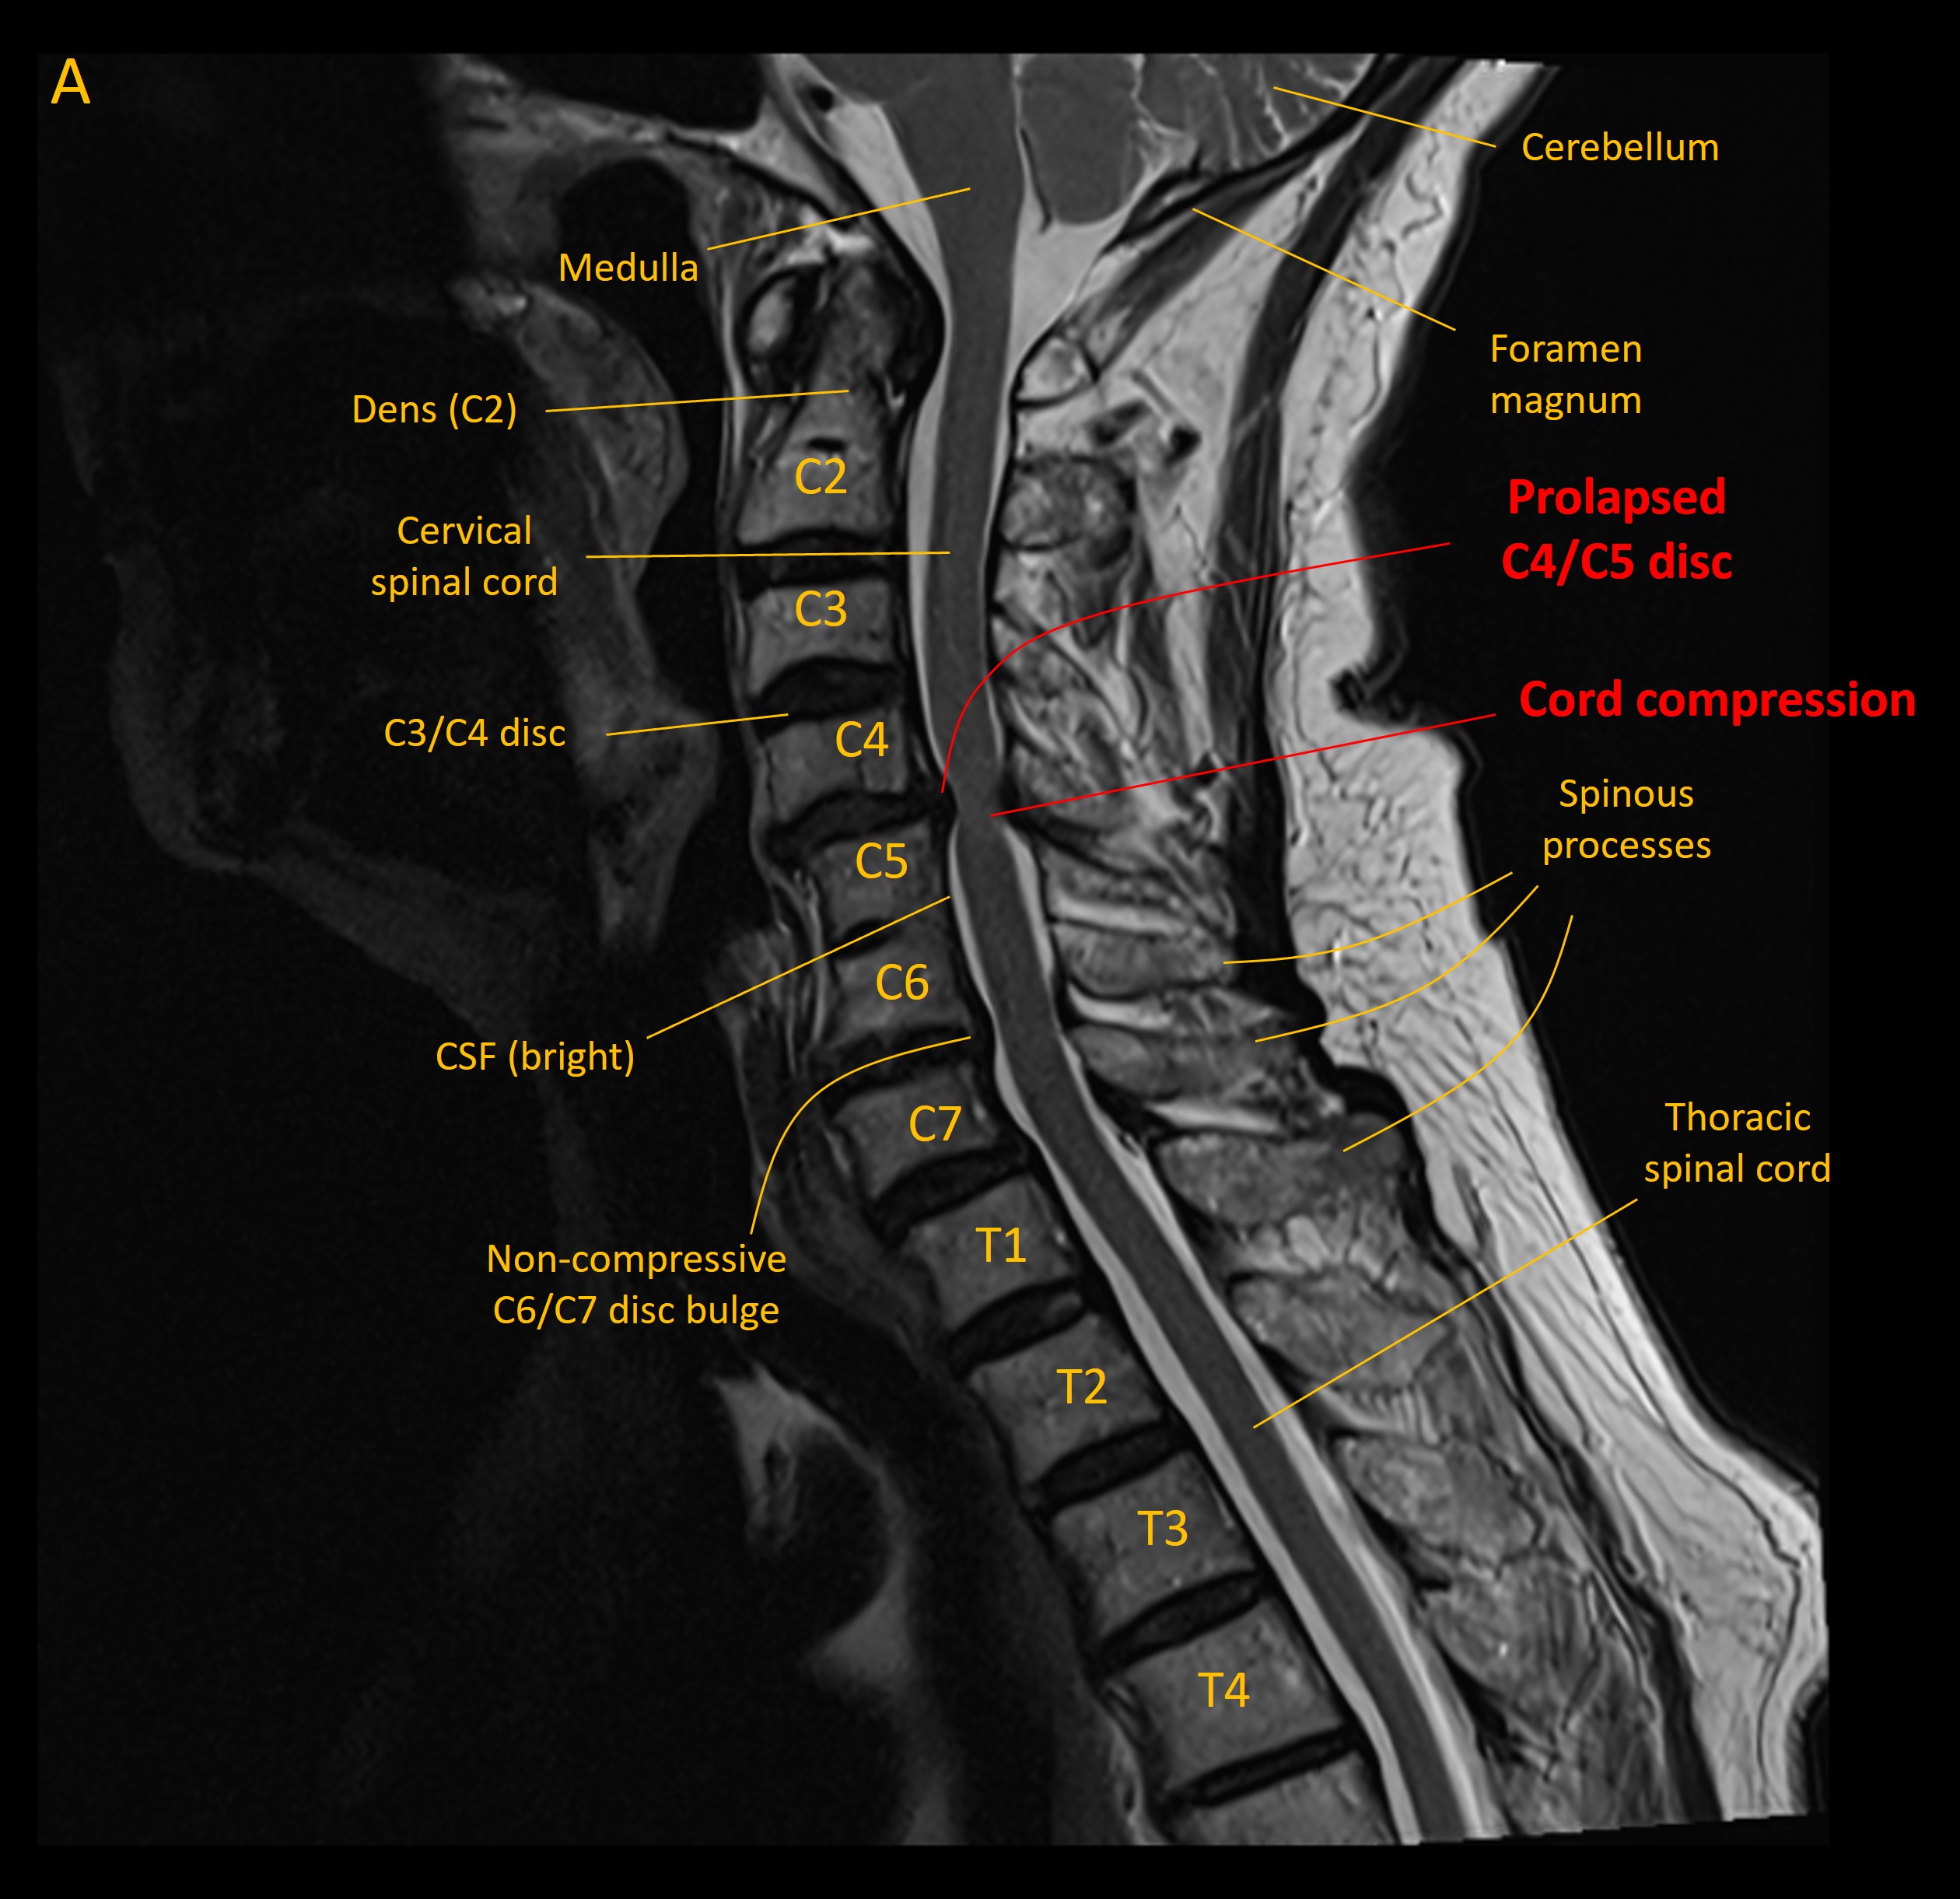

Urgent MRI spine demonstrated a C4/C5 disc prolapse compressing the spinal cord from in front (image A - sagittal view). Sagittal MRI

Degenerative changes were seen at multiple levels in the cervical spine, as is frequent at this age, and with some levels featuring mild narrowing of exit foramina and contact with nerve roots. These were evident at levels C3/C4 (B), C4/C5 (C) and C5/C6(D) - although none of these were clinically evident. Disc bulges at other levels did not compress the cord.